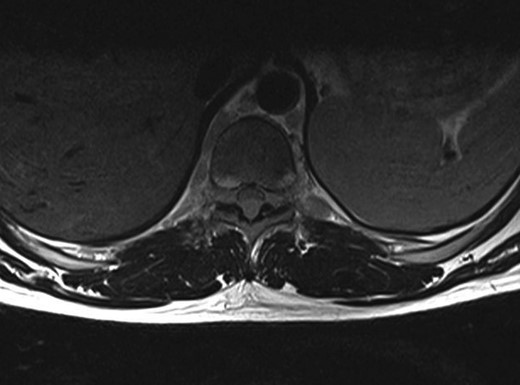

A 30-year-old male patient was admitted to our clinic with back pain. Pain was provoked by movements. The severity of pain was associated with the inability to perform the activities of daily living. The patient did not have any lymphoma-related B-type symptoms, including body weight loss, fever and sweat at night. He did not have a past and family history. There was no neurological deficit. Routine laboratory test results were normal. A magnetic resonance imaging (MRI) scan of the thoracic spine demonstrated an epidural tumor at the T9–11 level (Figs 1–3). The patient underwent spinal cord decompression via total laminectomy of T9–11 levels. Subtotal resection of the tumor was performed. Histological examination revealed the polymorphous cellular infiltration by histiocytes, large mononuclear cells and lacunar Reed–Sternberg cells with folded multi-lobed nuclei and small nucleoli (Fig. 4). Immunohistochemical staining was positive for CD15 and CD30 and negative for CD3, CD20, CD79a or CD45Ro. These features were most frequently observed in the mixed cellularity type of Hodgkin's lymphoma. Histological examination of the vertrebral body revealed no abnormality. The results of all other examinations (F-18 fluorodeoxyglucose positron emission tomography (F-18 FDG PET/CT), bone marrow biopsy and computed tomography (CT) of the chest, abdomen and pelvis) were negative for an occult disease. The patient was referred to the hematology department to undergo staged treatment. Six courses of chemotheraphy containing ABVD regimen (adriamycin, bleomycin, vinblastine and dacarbazine) were given to the patient. Postoperative MRI scan did not reveal any evidence of Hodgkin's disease (Fig. 5), F-18 FDG PET/CT, CT of the chest, abdomen and pelvis were obtained in 24 months and did not reveal any evidence of Hodgkin's disease.

Moridaira et al. [4] reported a case of Hodgkin's disease at T8–10 epidural space. Rao et al. [6] published a case with primary spinal epidural Hodgkin's lymphoma. Our case is apparently the seventh case to be diagnosed with Hodgkin's disease who presented with spinal cord compression due to epidural space without lymphoma elsewhere. The abnormal MRI marrow signal of the T9 and T10 vertebral bodies can be seen in Fig. 5. Maybe the tumor in fact originated within the abnormal T9 or T10 bone marrow and spread to the epidural space via the epidural venous plexus. But histological examination of the vertebral body revealed no abnormality.